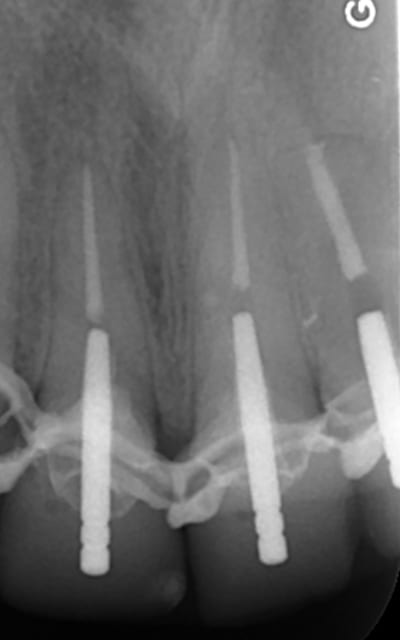

Zoom incisives eb4rim - Eugenol

Retraitement et cour prov ej8sen - Eugenol

Canaux calcifi s e685ou - Eugenol

Avec provisoires o4ho8c - Eugenol

Sur les monoradiculées, les tenons sont un peu trop courts. Avec les années, si l'os alvéolaire diminue, les risques de fractures de racines augmentent lorsque le bout du tenon se retrouve au niveau du rebord alvéolaire.

Stop à 11 mm pivomatic bleu dans mon cas au delà le pivot calcinable bleu est trop court( après faut passer au vert). Mais ca suffit amplement.

je fait extrêmement peu de tenon, mais tu nous présentes un travail soigné au moins d'un point de vue radiologique, sur la technique endo intrinsèque je laisse le soin a chacun de se faire une opinion